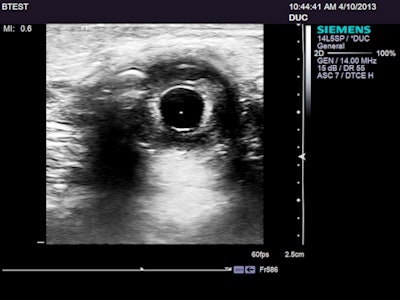

From the start of testing: my left iris and pupil; the central reflector is a Mittendorf spot. The image was converted to grayscale and the contrast was enhanced. This is a good target for assessing lateral resolution spread, dynamic range, and image noise, as well as how much of the display matrix is devoted to the ultrasound image. It is also excellent for assessing dynamics by following changes in pupil size with emotion and changes in ambient light.A disappointing start